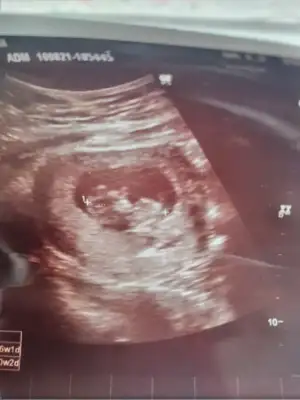

Kızlar merhaba, tahminde bulunabilir misiniz acaba? Doktor bir şey diyemedi çok haraketli olduğu için 🤗🤗 12+2 günlük

Ikra meyra Ikra meyra bana da bir tahmininiz var mıııı 🙆‍♀️🙆‍♀️🙆‍♀️ yukarıda gözükmedi sanırım tekrar ekliyorum çok merak ediyorum da 🤗🤗🤗🙏🙏🙏🙏teşekkür ederim 💘💘 12+2 günlük burda

• IMG_20210820_133934.webp

IMG_20210820_133934.webp

12,8 KB · Görüntüleme: 122

• IMG_20210820_133911.webp

IMG_20210820_133911.webp

16,3 KB · Görüntüleme: 92